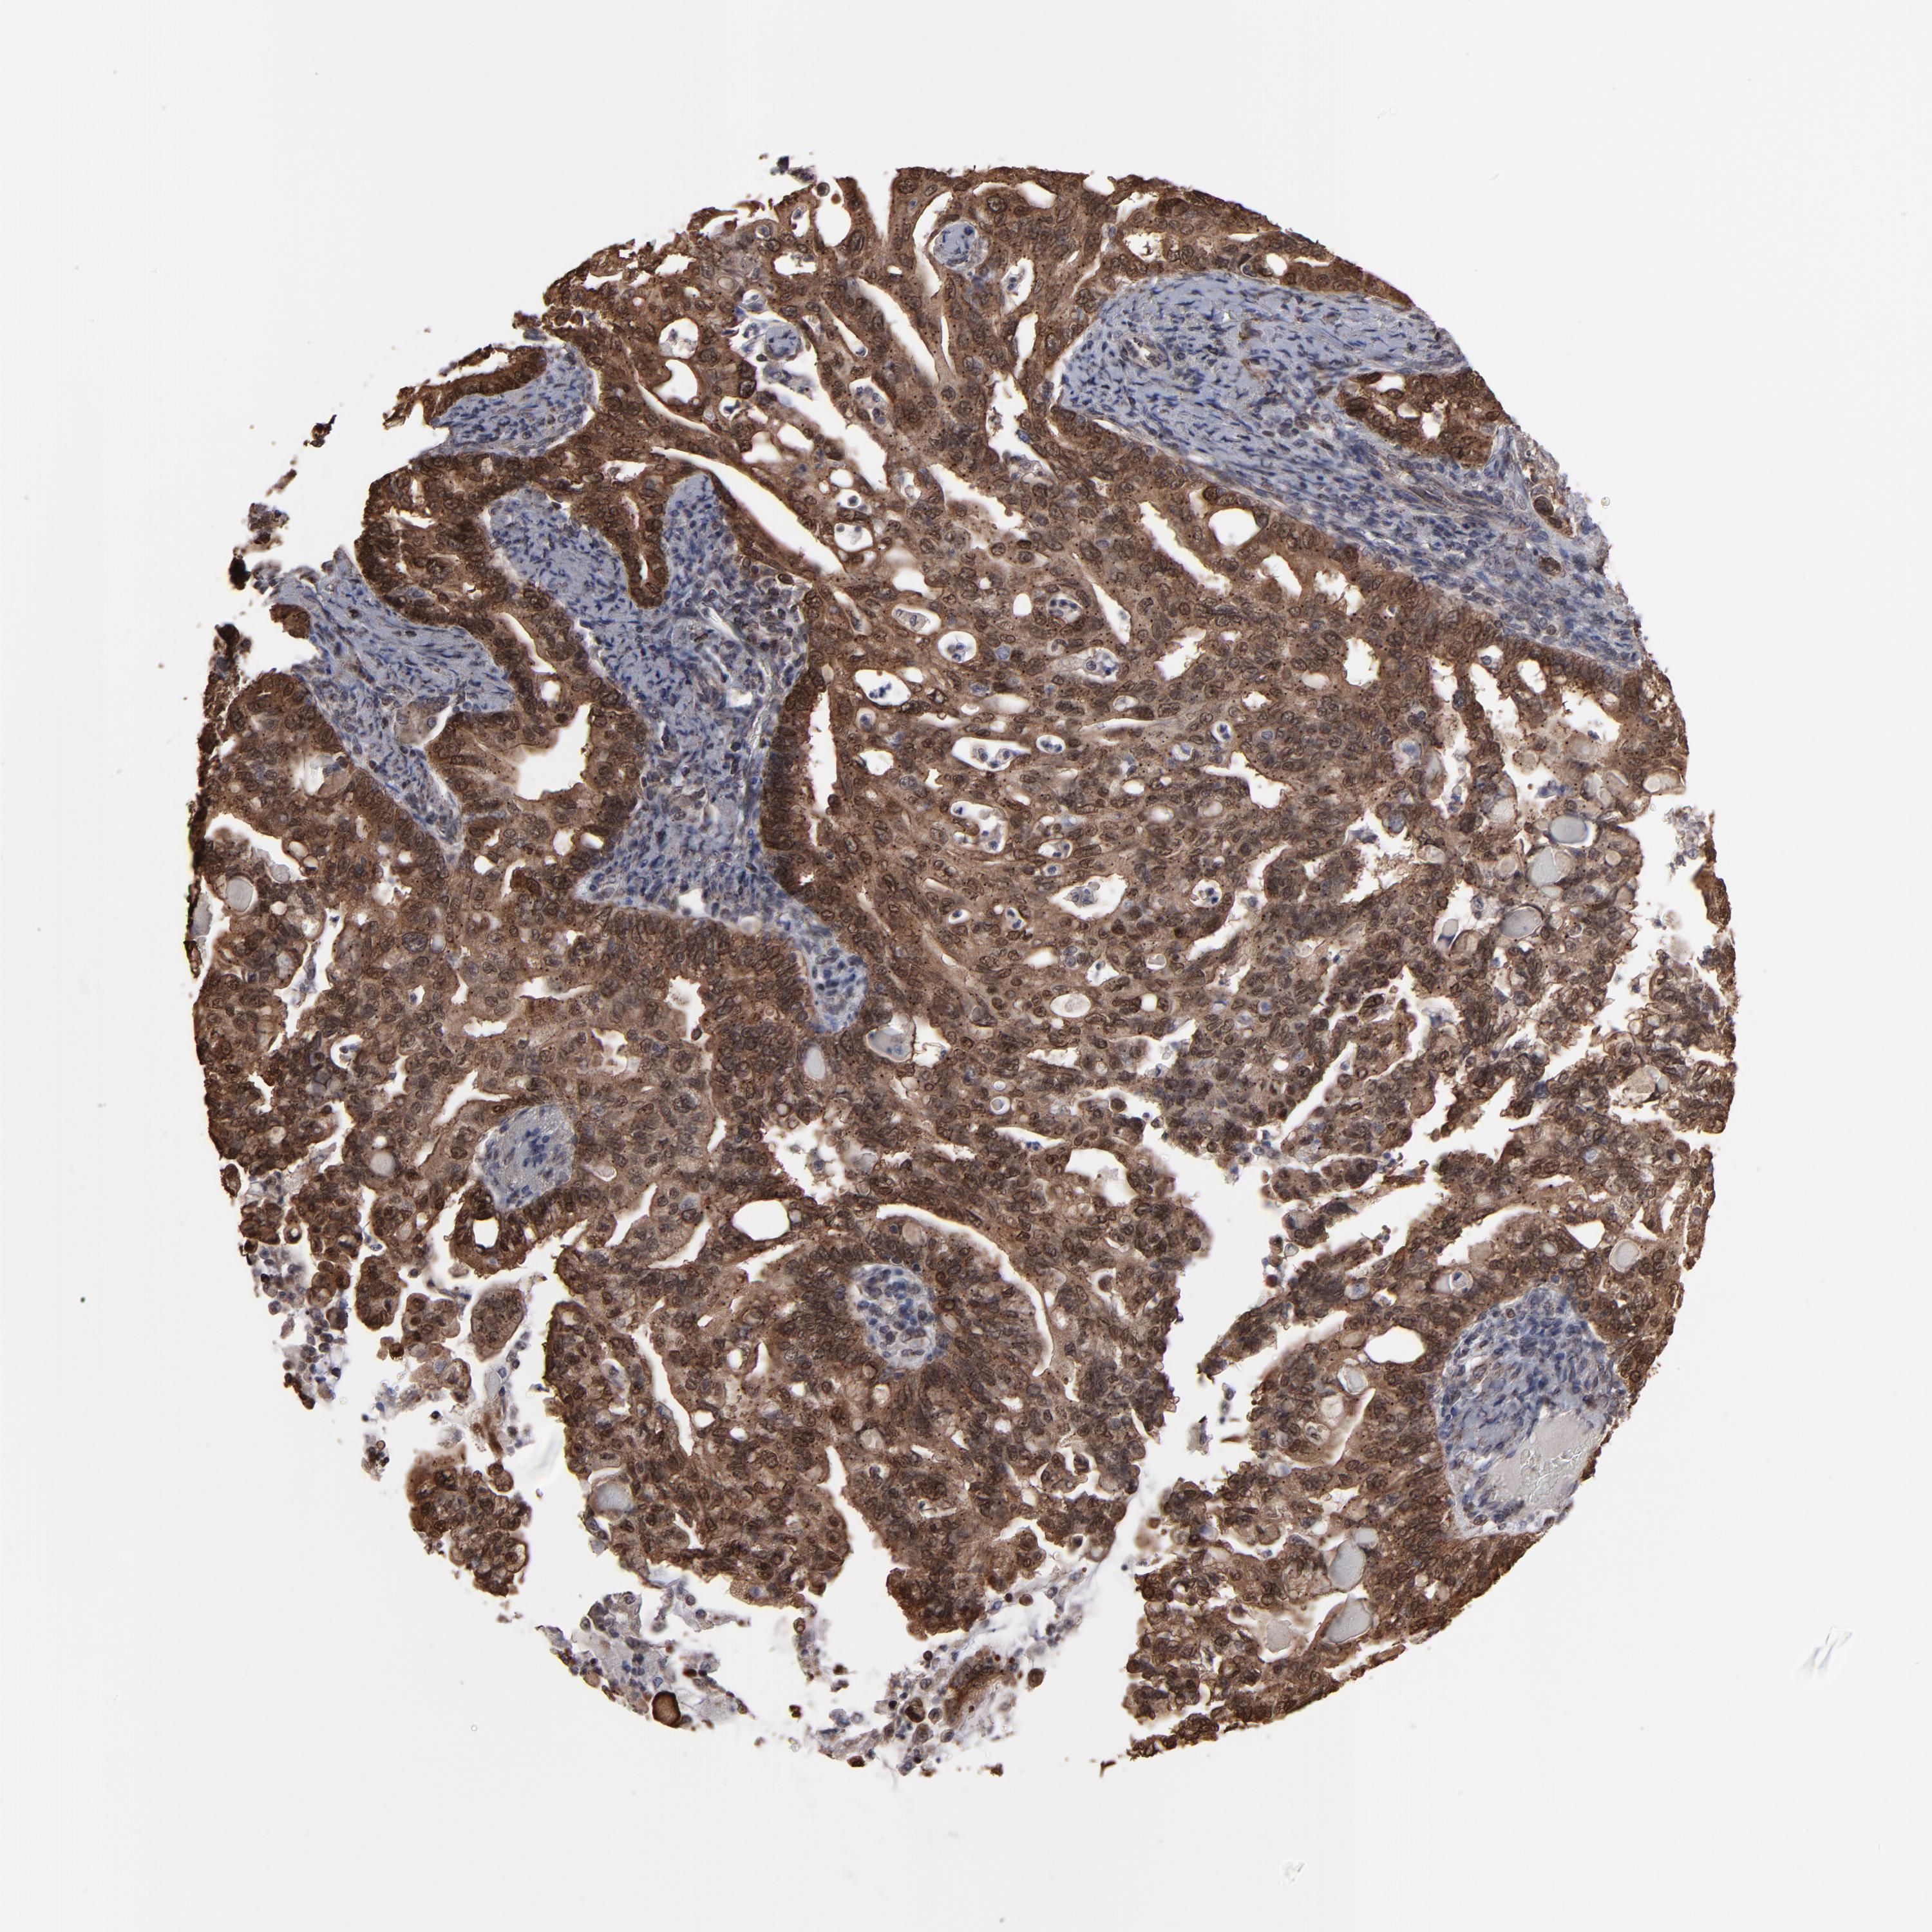

PANCREATIC CANCER - Protein expressioni

A mouse-over function shows sample information and annotation data. Click on an image to view it in a full screen mode. Samples can be filtered based on level of antibody staining by selecting one or several of the following categories: high, medium, low and not detected. The assay and annotation is described here.

Note that samples used for immunohistochemistry by the Human Protein Atlas do not correspond to samples in the TCGA dataset.

Antibody stainingi

Antibody staining in the annotated cell types in the current human tissue is reported as not detected, low, medium, or high, based on conventional immunohistochemistry profiling in selected tissues. This score is based on the combination of the staining intensity and fraction of stained cells.

Each image is clickable and will lead to virtual microscopy that enables deeper exploration of all samples and also displays staining intensity scores, fraction scores and subcellular localization as well as patient and tissue information for each sample.

Antibody HPA002109

Staining

High

Medium

Low

Not detected

Intensity

Strong

Moderate

Weak

Negative

Quantity

>75%

75%-25%

<25%

None

Location

Nuclear

Cytoplasmic/membranous

Cytoplasmic/membranous,nuclear

Adenocarcinoma, NOS

Adenocarcinoma, metastatic, NOS